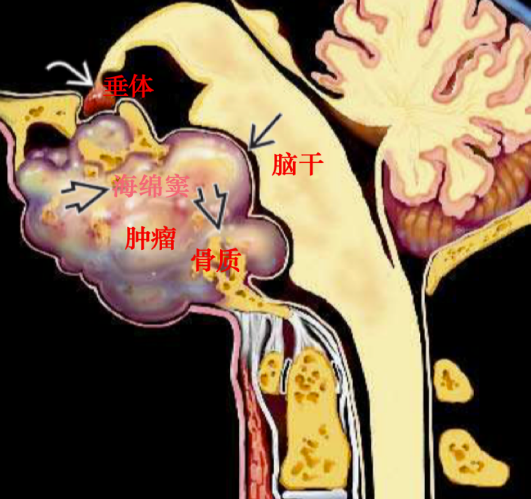

INC国际神经外科顾问团之 国际神经外科联合会WFNS颅底手术委员会主席 法国Sebastien Froelich教授手术纪实 噫吁嚱!危乎难哉!脊索瘤手术之难,难在何处?一是肿瘤高度恶性,二是所在位...

颅内脊索瘤如何治疗?颅内脊索瘤就是指发生在脑内的颅内脊索瘤,是颅内少见的的一种损害性肿瘤,深在于颅底部位,也是难以治疗的脑肿瘤之一。1857年由Virchow首先记载脊索瘤,1...

脊索瘤是恶性肿瘤 ,其缓慢增长并转移到身体的其他器官。肿瘤起源于胎儿发育早期的脊索。在55岁以上的人群中,这种现象更为明显,尽管年轻人可能会受到影响。脊索瘤严重威胁生...